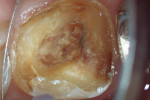

According to the classification system of the American Endodontics Association, tooth No. 36 had a pulpal and periapical diagnosis of irreversible inflammatory pulpitis with normal periapex, for which endodontic treatment is indicated (Figure 1 through Figure 3).6

The treatment was conducted in its entirety using an operative microscope, with magnification varying between 2.5X and 12.5X. The pulp chamber was accessed with a 1013 spherical diamond bit followed by a 3082 conical-truck diamond bit (Figure 4), and the finishing was done with a conical-truck diamond ultrasonic tip (Helse, E7D). After location of the canals, a No. 10 type K file was slowly introduced until reaching two-thirds of the initial x-ray length of the tooth. This was followed by a No. 25.06 reciprocating instrument (Reciproc, VDW) with apical progression in sequences of three movements around 1mm in amplitude in the apical direction. Following each sequence of three movements with the reciprocating instrument, irrigation was performed with 5ml of 2.5% sodium hypochlorite, and a No. 10 type K file was taken to two-thirds of the x-ray length of the tooth. This procedure was repeated until the reciprocating instruments reached this pre-established length.

To complete the procedure, the Fillapex MTA cement was prepared and introduced into the canals using the main gutta-percha cones (Figure 6). The excess material from the cones was cut using a heat transfer system (Touch'n Heat Sybron Endo) and cold-compressed vertically. The pulp chamber was sealed with photopolymerizable composite resin, and the patient was sent to her dentist for a definitive restoration of the dental element (Figure 7). After 17 months, the patient returned for a control consultation, and an evaluation of her x-ray images indicated endodontic success characterized by the absence of signs and symptoms, the physiologic function of the tooth, the normality of the periapex, and the reabsorption of the surplus Fillapex MTA cement (Figure 8).